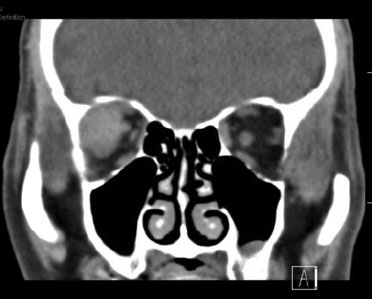

Course: A computed tomography (CT) scan demonstrated a right lateral extraconal well-demarcated mass and proptosis OD (Figure 1). A diagnosis of spontaneous retrobulbar hemorrhage was made due to the rapid onset of symptoms, presence of an extraconal lesion consistent with a hematoma on CT and moderate proptosis. CT angiography was performed and was negative for AV malformation, varix, or other vascular abnormality. Serial intraocular pressure (IOP) checks were performed and the IOP increased into the 40s with return of symptoms of nausea. We performed a complete right inferior and superior cantholysis and his IOP subsequently came back down to 30mmHg with improvement of nausea. His central retinal artery remained perfused. He received 250mg IV acetazolamide as well as repeat doses of topical dorzolamide/timolol and brimonidine. He was admitted overnight for observation and discharged home on brimonidine and dorzolamide/timolol twice daily, OD. One week later the patient was again seen in the emergency room for right sided headache and nausea. His visual acuity OD was 20/320 and IOP OD was 18mmHg. Repeat CT showed mild enlargement of the hematoma with increased medial buckling of the right optic nerve (Figure 2). No immediate intervention was performed and the patient followed up in the oculoplastics clinic three days later. The patient's visual acuity was 20/125 OD and a central scotoma OD was found on Goldmann visual field test suggesting optic nerve compression (Figure 3). A right lateral orbitotomy was performed two days later with drainage of the hematoma. One month later during clinic follow-up his visual acuity was 20/25 OD with a full visual field on repeat Goldmann visual field testing (Figure 4).

Figure 1: Axial and coronal views of soft tissue computed tomography (CT) of the orbit without contrast demonstrating a right lateral extraconal well-demarcated mass and proptosis OD.

computed tomography (CT) of the orbit without contrast demonstrating a right lateral extraconal well-demarcated mass and proptosis computed tomography (CT) of the orbit without contrast demonstrating a right lateral extraconal well-demarcated mass and proptosis

Figure 2: Soft tissue computed tomography of the orbit without contrast demonstrating right lateral extraconal mass with increased buckling of the optic nerve.

Soft tissue CT of the orbit without contrast demonstrating right lateral extraconal mass with increased buckling of the optic nerve